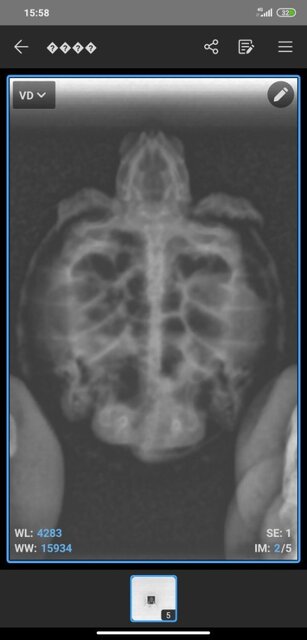

1760179420857.jpg

1760179420854.jpg

1760179420850.jpg

1760179420844.jpg

1760179381867.jpg